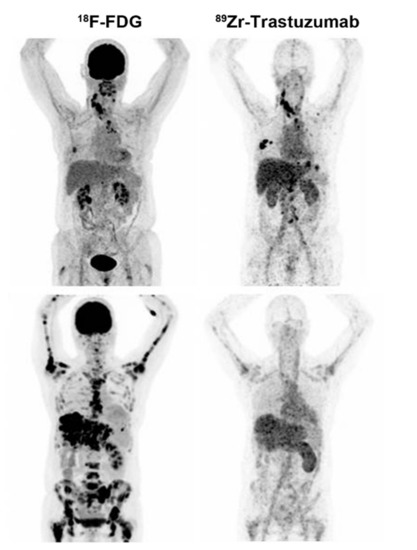

- Dijkers, E.C.; Oude Munnink, T.H.; Kosterink, J.G.; Brouwers, A.H.; Jager, P.L.; de Jong, J.R.; van Dongen, G.A.; Schröder, C.P.; Lub-de Hooge, M.N.; de Vries, E.G. Biodistribution of 89Zr-trastuzumab and PET Imaging of HER2-Positive Lesions in Patients With Metastatic Breast Cancer. Clin. Pharmacol. Ther. 2010, 87, 586–592. [Google Scholar] [CrossRef]

| HER2 | PET | Antibody | 89Zr-trastuzumab | 1. Radiolabeling efficiency: 77.6 ± 3.9% 2. Radiochemical purity: 98.1 ± 1.1% | 1. Low sensitivity 2. Liver and spleen had higher uptake | [15] | |